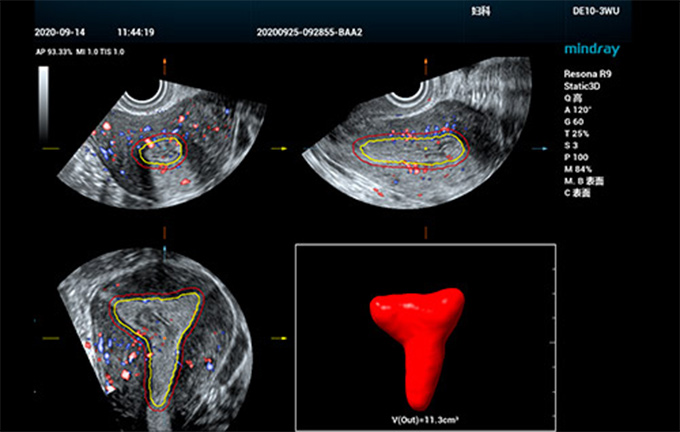

Smart ERA

Mindray, jinekolojik ultrason te?hisinin verimlili?ini ve do?rulu?unu art?rmak, Þreme sistemi bozukluklar?n?n ve tÞm?rlerin erken te?hisini daha eri?ilebilir hale getirmek amac?yla, doktorlar?n folikÞl ve rahim ultrason muayeneleri i?in verimli klinik te?his koymas?na yard?mc? olacak bir dizi ak?ll? ??zÞm geli?tirdi. Endometriyal reseptivite muayenesi gereksinimlerine yan?t veren, sekt?rÞn ilk tam otomatik endometriyal reseptivite analiz arac? olan Smart ERA, farkl? tip yap?lar i?in dahi 3B otomatik endometriyal g?rÞntÞleme yap?lmas?n? sa?lar. Endometriyal hacim ve kal?nl???n yan? s?ra, endometriyal kan ak?? indeksinin otomatik ?l?ÞmÞnÞ destekler. GÞ?lendirilmi? operasyon sÞreci, muayene tutarl?l???n? ve te?his verimlili?ini ?nemli ?l?Þde art?rarak, sonografi uzmanlar?n?n gebelik ?ncesi de?erlendirmeyi daha yÞksek ?zgÞvenle ve kolayca ger?ekle?tirmesine olanak tan?r.